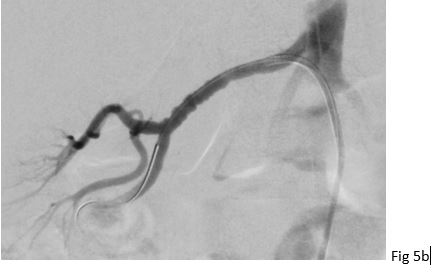

Figure 5: 37 year old female with fibromuscular dysplasia of the right renal artery. Digital subtraction angiography (DSA) showing the classical "string of beads" appearance of the right renal artery with stenosis in the mid segment in (a). DSA after ballon angioplasty without relevant stenosis in (b).